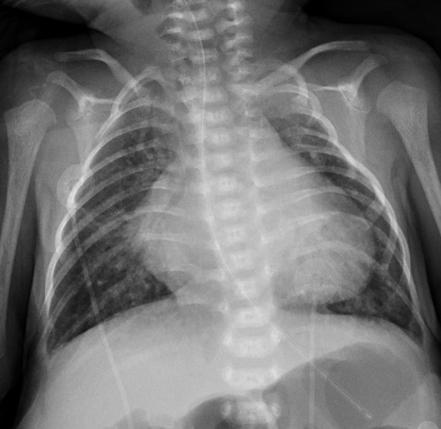

What might you see on a CXR in VSD? (4 things)

1. Cardiomegaly 1. Pulm oedema 1. Pleural effusion 1. Pulm HTN

What is Pulm Plethora?

A

Appearance of increased pulm perfusion on CXR